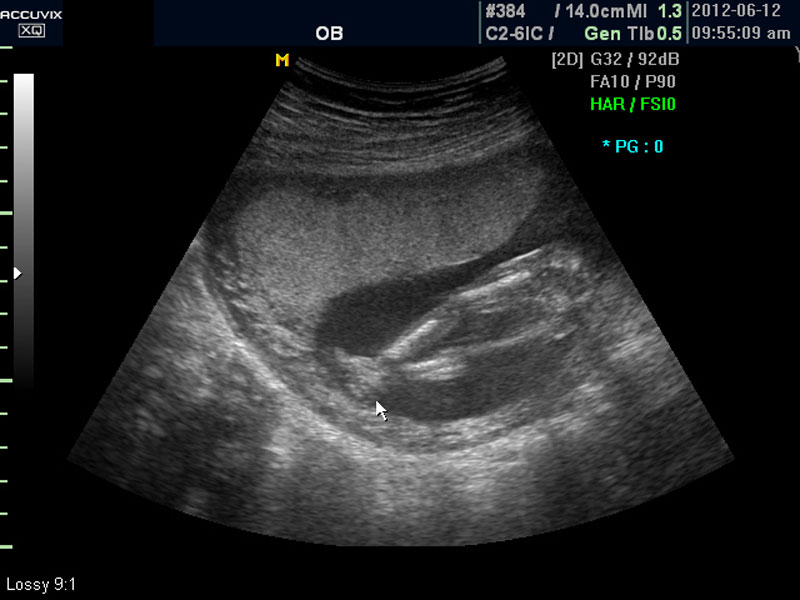

태아에 대한 관찰이 끝나면 태반의 위치와 양수의 양을 살펴 보는데 아직 태반의 위치는 고정된 것이 아니라 크게 의미는 없지만 이때부터의 위치는 대체로 임신 후반까지 크게 바뀌는 것은 아니며 또한 완전 전치 태반과 같은 경우는 임신 중기부터 출혈등의 증상이 나타날 수 있어 관찰이 필요한 대상입니다.

화면에서는 위쪽에 하얗게 균일하게 보이는 것이 태반의 모습입니다.

태반은 실제로 보면 피자처럼 둥그런 원판 모양이며 임신 후기로 갈수록 태아와 마찬가지로 크기가 커지고 두꺼워집니다.

양수의 양은 태아의 건강과 관련된 지표로 너무 많거나 너무 적으면 좋지 않은데 그 절대양을 측정할 수는 없어서 양수가 많은 부분의 깊이를 측정하거나 혹은 개략적으로 전체에서 차지하는 부분을 봐서 이상 여부를 판단합니다.

사진에서 검게 보이는 것이 양수입니다. 양수에 대하여는 색깔이나 밀도 등 다른 요소는 알기 어려워서 그 양만 가지고 판단을 하게 됩니다.